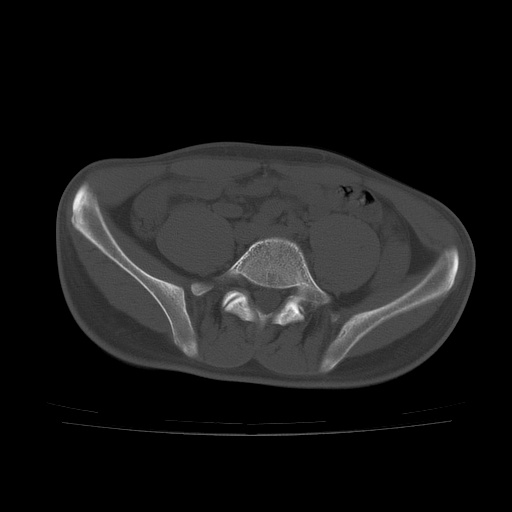

患者男性,18岁 腰腿痛1年  骶髂关节改变本人考虑强直性脊柱炎。

两侧骶髂关节骨质破坏,关节面毛糙,符合强直性脊柱炎骶髂关节改变。

符合强直性脊柱炎,虫蚀样骨质破坏。

两侧骶髂关节骨质破坏,关节面呈锯齿样改变关节间隙变窄,考虑强真性脊柱炎

双侧骶髂关节关节间隙变窄,边缘毛糙,关节面硬化,可见囊变!符合强直变现!

两侧骶髂关节骨质破坏以髂骨为主,间隙变窄,强直性脊柱炎